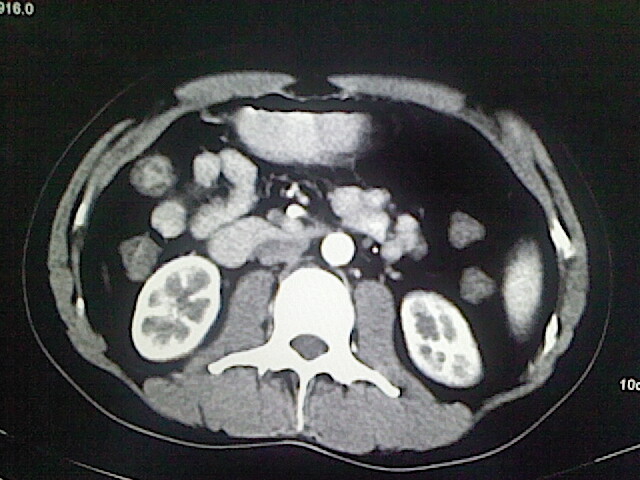

以下是引用卜一在2009-3-14 9:49:00的发言:[br]胆囊萎缩,胆囊壁不规则增厚,内部结构模糊,增强明显强化。另:肝左叶外侧段肝囊肿。支持:慢性胆囊炎!高度可疑:胆囊癌!

以下是引用余辉在2009-3-14 8:48:00的发言:[br]1)慢性胆囊炎。2)肝左叶外侧段肝囊肿。3)脂肪肝。[br]支持,胆囊萎缩,密度增高,不知b超具体有何提示,钙胆汁?结石?

以下是引用jiangjing在2009-3-14 10:18:00的发言:[br]1)慢性胆囊炎。2)肝左叶外侧段肝囊肿。3)脂肪肝。4.】建议行肝功能检查